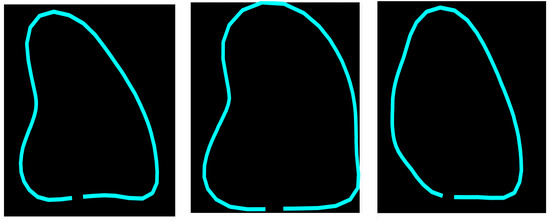

3.1. Point Distribution Model of the Left Ventricle (LV-PDM)

Point distribution models (PDMs) provide a compact representation of a class of shapes; in this case, the shape of the left ventricle. Construction of the PDM was performed as described in [30] by annotating landmark points around the contour of each left ventricle previously marked by an expert. For this LV-PDM, 64 landmarks were selected, which accurately represent the contour of the left ventricle, as shown in Figure 2, using the training data described in Section 4.1. Principal component analysis (PCA) of the normalized landmark training set resulted in five principal modes of variation in the shape of the LV, contained in a principal eigenvector matrix (), which allows creating new instances of the LV shape using Equation (1). Figure 3 shows some examples of shapes, corresponding to different values of the five weights in vector b.

Figure 2.

Example of landmarks sampled in LV ultrasound images.

Figure 3.

Example of different shapes of the LV using the principal variation modes calculated from the PDM.